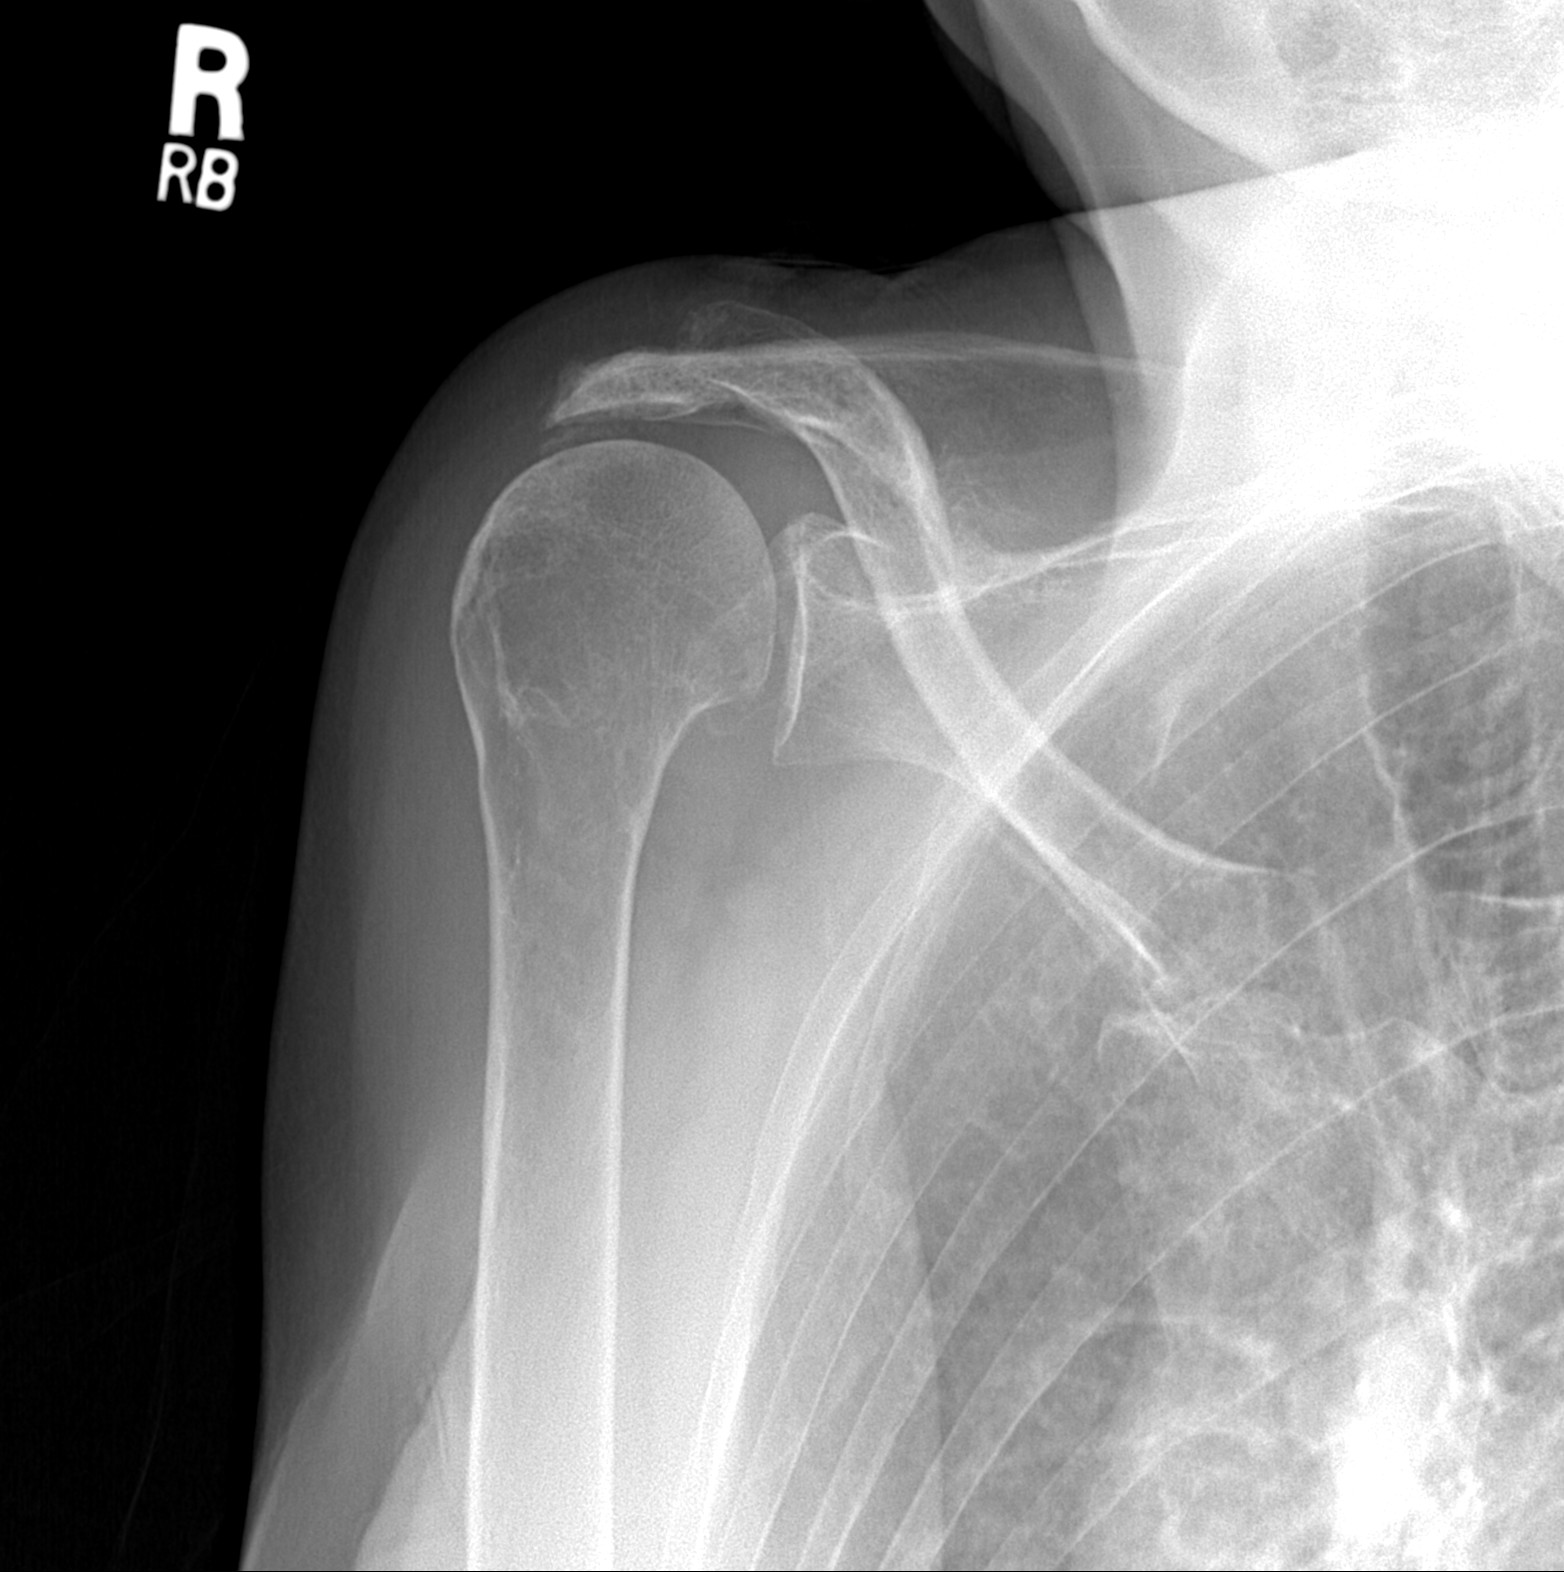

Below are the patient’s x-rays of the other shoulder taken at the same visit. What we see here is that the humeral head (the ball) is not in the center of the glenoid (the socket). It has moved upward out of the socket as a result of a massive chronic rotator cuff tear. If there were any cuff that could be fixed, it would not heal and would lead to a poor outcome.

This is another case that could benefit from a reverse should replacement if she had pain and an impairment that bothered her. The good thing is that this patient does not have any pain in her right shoulder. She has about 50% of a normal range of motion but has good function. I would leave well enough alone.